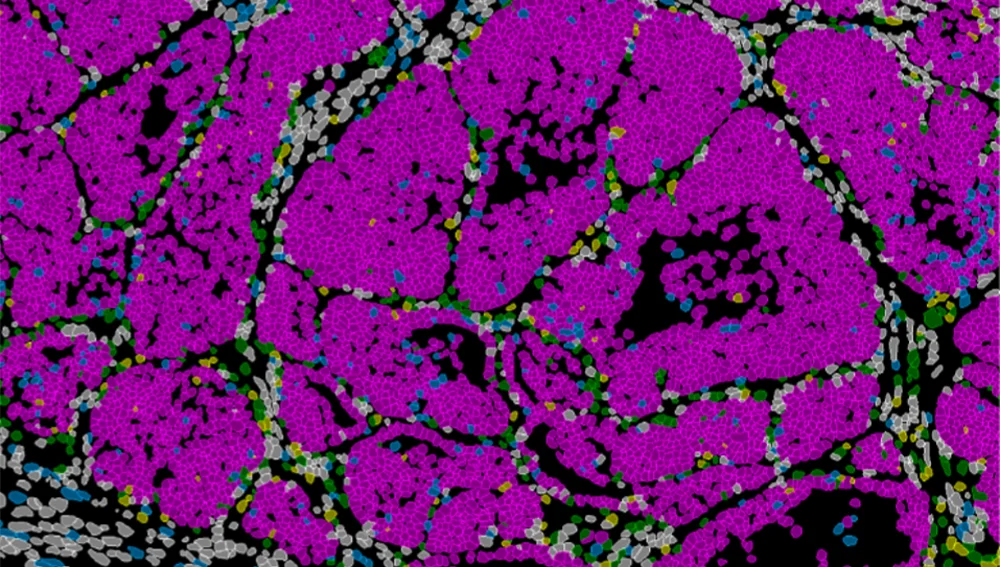

La investigación ha revelado que las células que dan lugar a metástasis pueden identificarse dentro del tumor primario. Los resultados muestran que en el borde invasivo del cáncer de mama existe una población concreta de células capaz de invadir y, al mismo tiempo, dividirse o entrar en estado de letargo. Este equilibrio determina que las células que se escapan del tumor puedan o no iniciar nuevos focos tumorales en órganos distantes, las metástasis.

Con ello la capacidad metastática no surge por azar ni depende únicamente del microambiente del órgano de destino. El potencial metastásico está determinado en un conjunto de células presentes en el tumor primario que origina el cáncer, que adoptan un estado altamente metastásico coordinado por un el gen identificado.